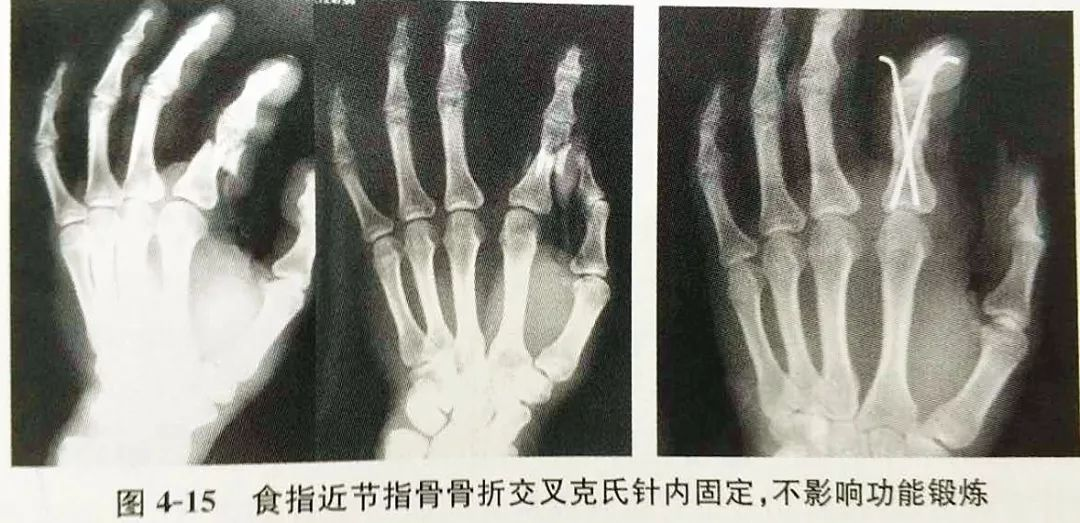

1、克氏针:克氏针内固定应用于临床已有70多年的历史,一直是掌指骨骨折最常用的内固定材料,其操作方便,经济实用,是最经典的内固定方式,如图4-15。作为治疗手部骨折最常用的内固定,目前仍被广泛采用。克氏针内固定的优点:①操作简便,使用非常灵活;②软组织剥离少,对骨折端血运影响小,手术创伤小,有利于骨折愈合;③二次取针容易;④费用低廉,应用范围广,对大部分手部骨折(如关节内骨折、严重粉碎性骨折及末节指骨骨折)均适用。克氏针内固定缺点:①相对钢板固定而言,稳定性较差,单枚克氏针不能控制短缩和旋转移位,通常需要2枚以上克氏针交叉固定;②骨折端无加压作用;③跨关节固定造成关节面破坏;④对关节的固定和对肌腱的阻挡,使手部关节不能进行早期锻炼而影响功能恢复。

现代的内固定技术及设备迅速发展,克氏针内固定手术也越来越精细,绝大部分已经能做到不跨关节固定,对关节周围软组织及肌腱损伤小,不影响术后早期关节功能训练。在C型臂X光机的帮助下,部分病例还可通过闭合复位克氏针内固定方式达到满意疗效,进一步减少手术对局部软组织的损伤及对骨折端血供的影响,从而促进骨折的愈合。克氏针内固定的注意事项:①用直径为1.0~1.2mm的克氏针固定较大骨块,根据骨折线的方向确定进针点和进针的方向;②以恢复力线为目的,关节内的骨折必须解剖复位和坚强固定;③不是所有的骨块都需要用克氏针来固定,在达到骨折端稳定的前提下,尽量少用克氏针;④克氏针不经过肌腱或指背腱膜固定,尽可能创造早期功能锻炼的机会;⑤要有严密的术前计划,术中不要重复操作,否则可能使骨折块更粉碎,甚至无法固定;⑥一般克氏针应放在皮内,以减少感染机会,取出时也并不难。